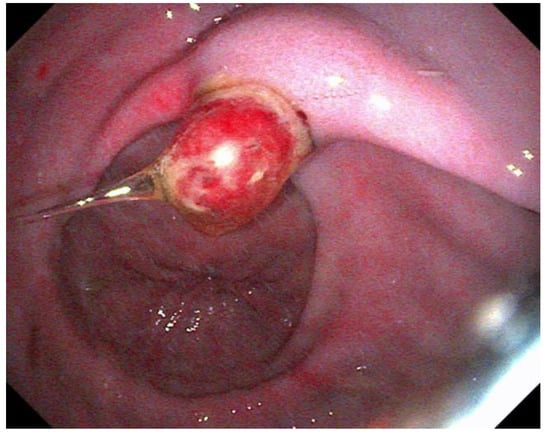

The use of histopathology to assess disease, especially of the glandular mucosa, is becoming increasingly described [67,88,119,120]. One study directly comparing gross EGGD to histopathological disease showed poor correlation, with 71% of grossly normal stomachs having mild gastritis, and all EGGD lesions demonstrating various degrees of gastritis histologically, regardless of gross severity [88]. Another study demonstrated both glandular gastric lymphoplasmacytic inflammation and eosinophilic infiltrate in a relatively small sample population [67]. The comparison of biopsy techniques feasible via endoscopy to full thickness samples post-mortem found the ‘double bite’ technique to yield the best samples for assessment [88]. Larger samples for histopathology are described using a snare when lesions are sufficiently raised, such as glandular polyps (Figure 1) [121].

Figure 1.

An adenomatous polyp in the pyloric region.